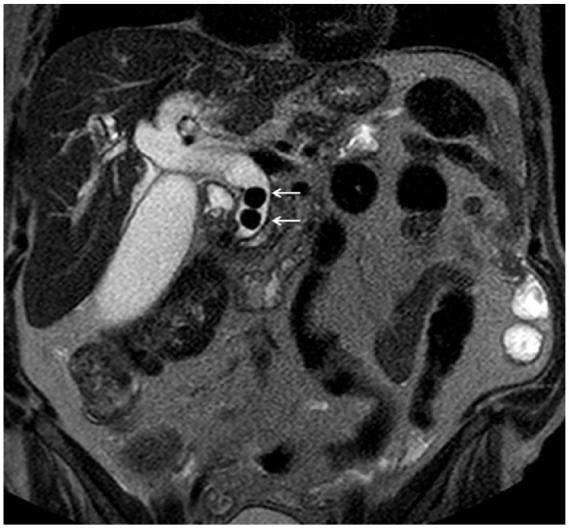

Splenic injury is an extremely rare complication of endoscopic retrograde cholangiopancreatography (ERCP). There are only 34 cases reported in the literature up to now. Based on a case of a 72-year-old man, who after ERCP due to choledocholithiasis developed a large perisplenic and subcapsular hematoma, we carried out an extensive review of all cases of ERCP-induced splenic injury found in the literature. We searched PubMed/Medline and Google Scholar till 15 April 2023, for published case reports and series using the following terms: splenic injury after ERCP, ERCP-induced splenic injury, and post-ERCP splenic trauma. The case reports included were in English, Spanish, and German literature. We attempt to discuss the possible clinical image, the available diagnostic methods, the potential treatment alternatives, and predisposing factors related to this entity. Furthermore, a theory of a possible mechanism of this injury is discussed and supported schematically. The ERCP-induced splenic injury is rare and a high index of suspicion is needed for diagnosis. Therefore, we present two diagnostic algorithms, which according to our opinion may assist the evaluation of this complication and lead to early accurate diagnosis and appropriate management. Collectively, our findings support that although ERCP-induced splenic injury is an unexpected/unusual complication of ERCP, following the proper steps can be timely diagnosed and treated.